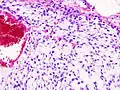

![]() Гистограмма хондромы стенки грудной клетки. Окрашено гематоксилином и эозином. | |

Хондросаркома — злокачественная опухоль хрящевого строения. Хондросаркома периферической локализации хорошо выявляется в виде плотной опухоли, прилегающей к кортикальному слою кости, иногда прорастающей в кость на различную глубину. В ней могут быть очаги оссификации и петрификаты. Опухоль плотноэластической консистенции, при наличии ослизнения, распада или кровоизлияний — более мягкая, не имеет ясного ограничения от соседней ткани. При разрезе нетрудно определить хрящевой её характер. При микроскопическом исследовании опухоль напоминает иногда хондрому, состоит из незрелых клеток с резко выраженным клеточным атипизмом. Часто рисунок опухоли имеет вид микросаркомы, в которой можно найти участки хрящевой ткани с плохо оформленными ячейками, содержащие неправильной формы хондробласты.